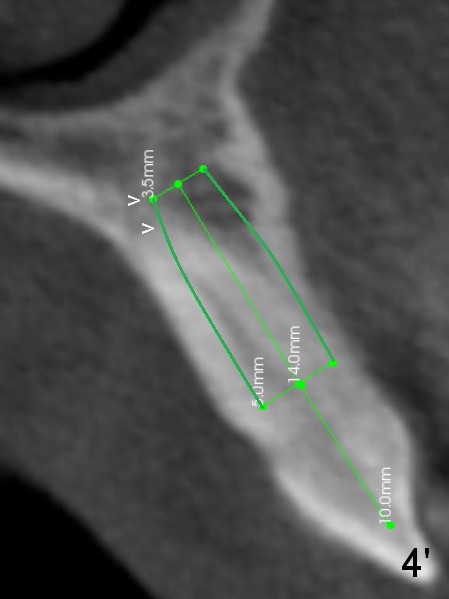

Lengthwise, a longer osteotomy is needed (Fig.4): 20 mm at the gingival level, 17 mm at the bone level. Distal to the 5 mm tap is a gap (*). Initially a shorter osteotomy (by 3 mm) is made: there is minimal engagement with the labial bone (Fig.4' between arrowheads (CT coronal section from not the same patient)). The osteotomy is extended (Fig.4''). This is the second problem to be solved.